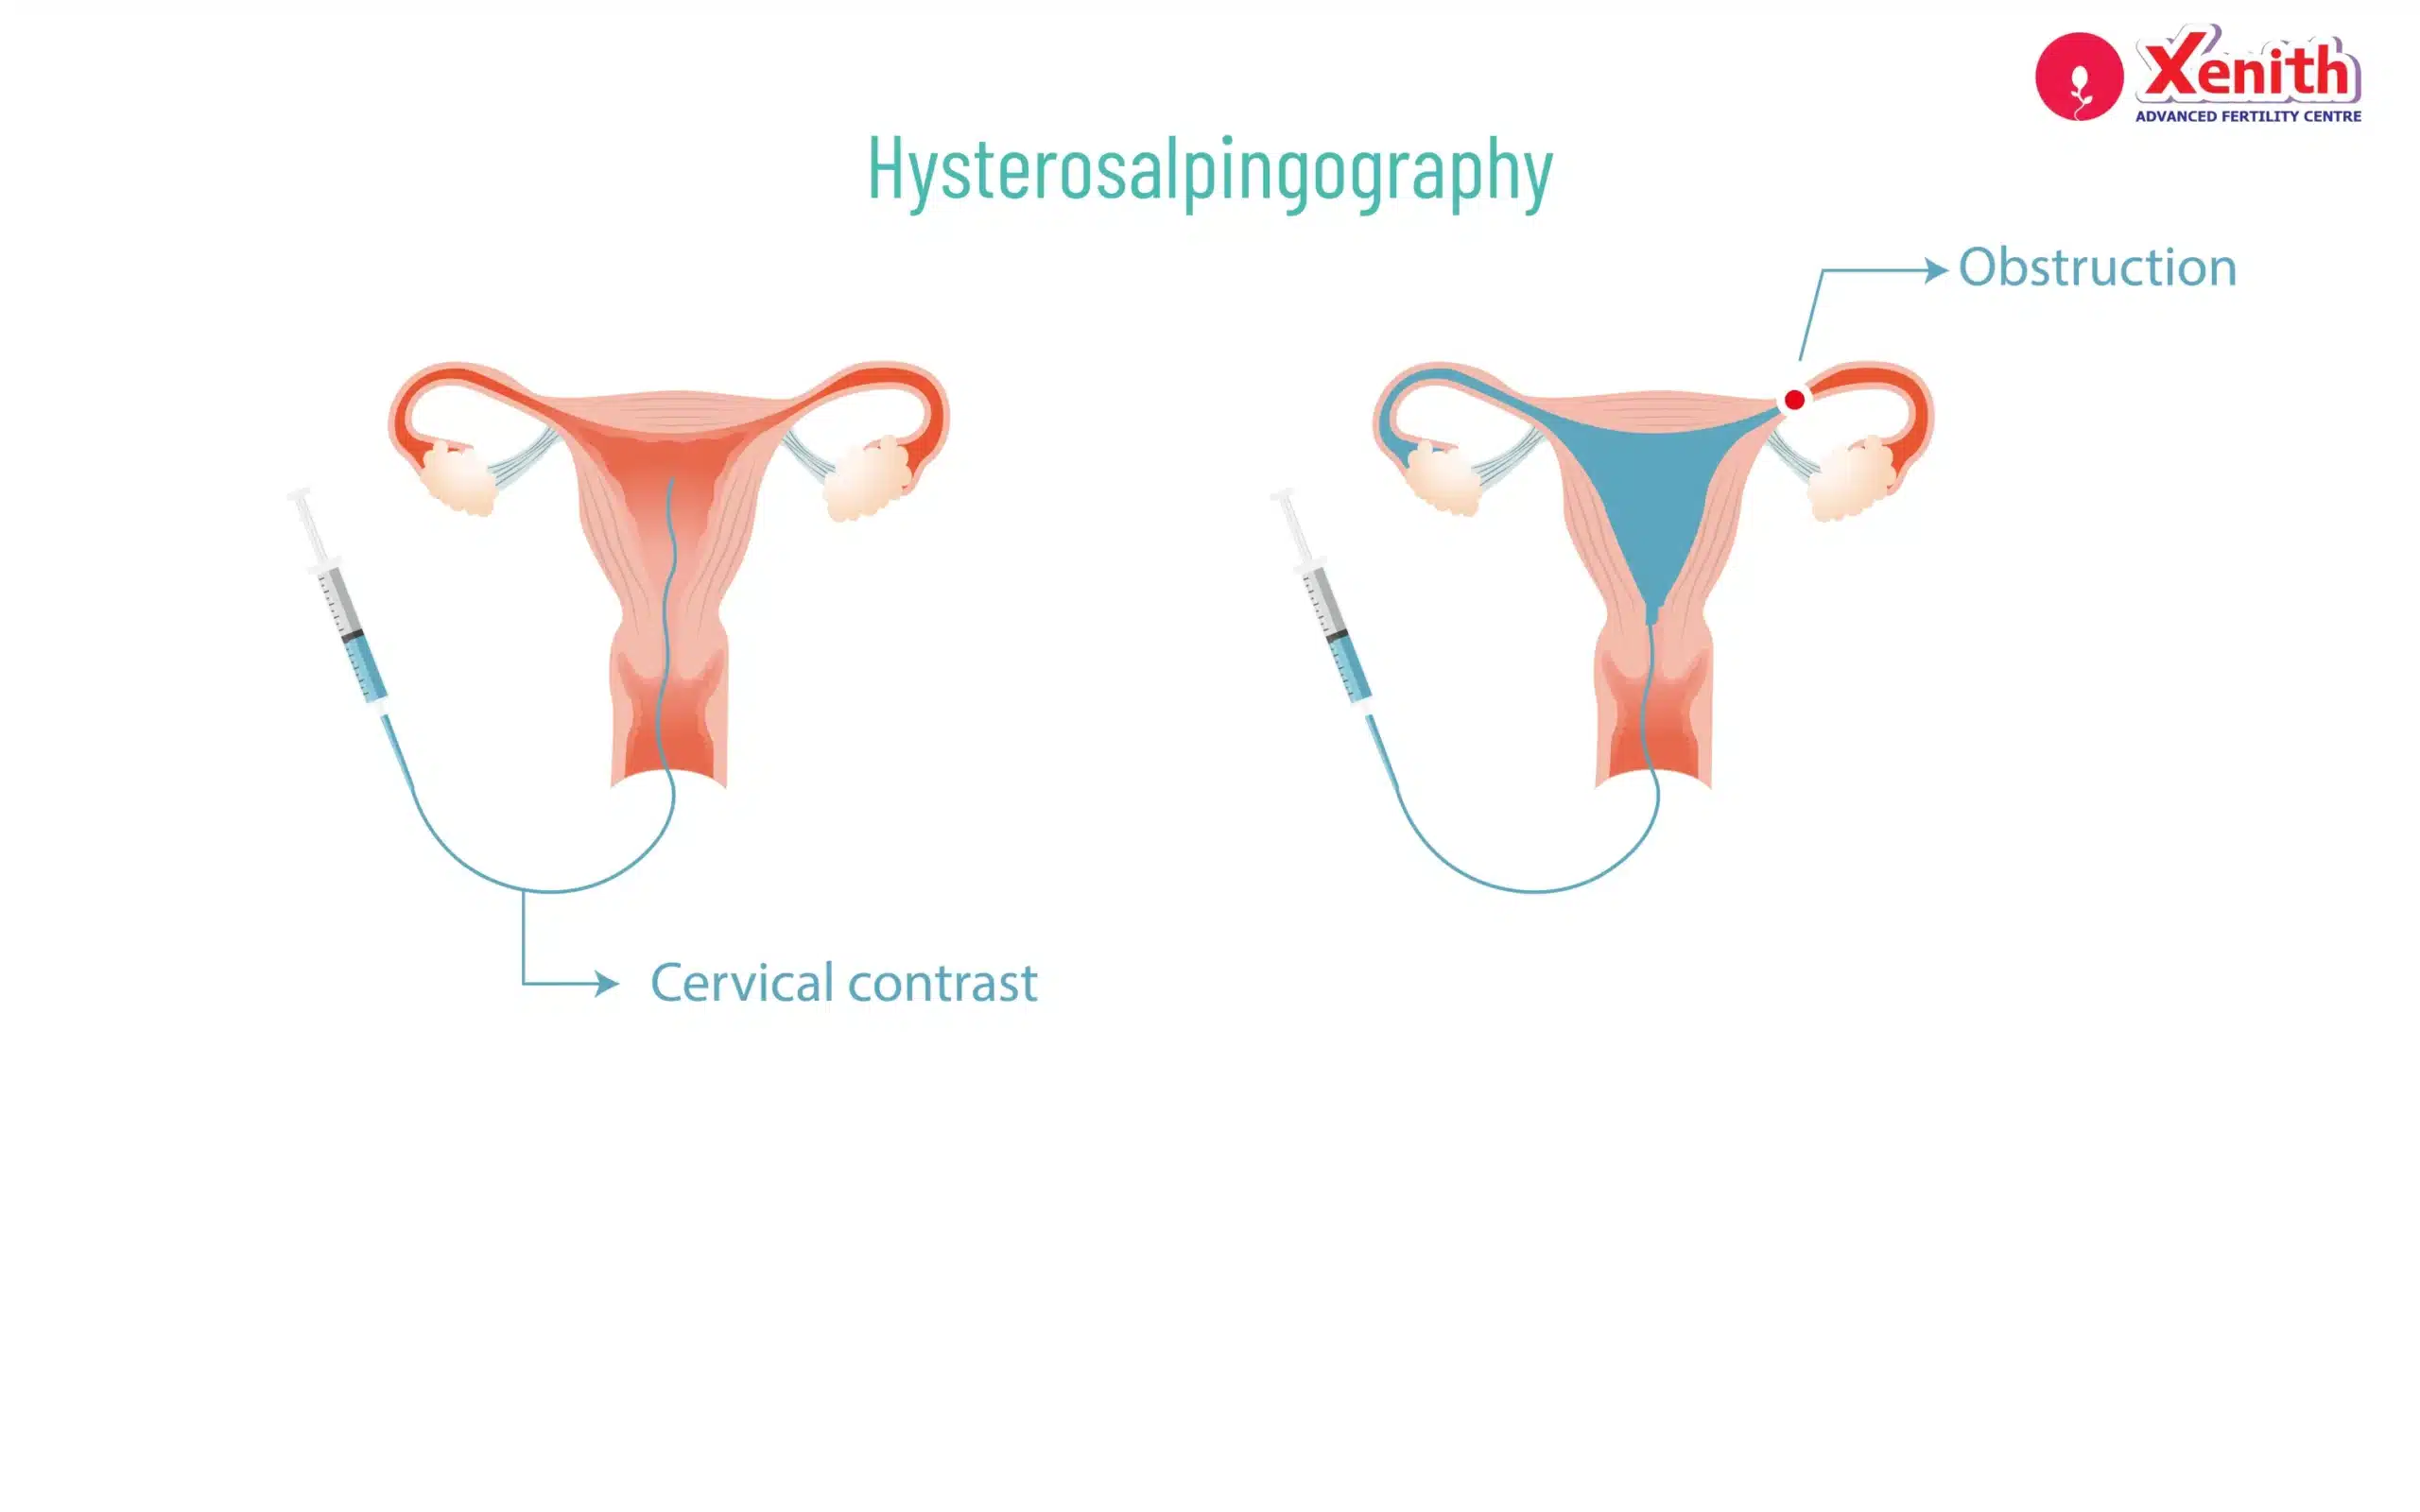

One of the most important tests in female fertility evaluation is the Hysterosalpingogram (HSG). In simple terms, an HSG test is a special type of X-ray that helps doctors see the inside of the uterus and fallopian tubes. It helps identify whether the fallopian tubes are open or blocked and whether the uterus has any structural issues.

- Injection of contrast dye: A thin tube (catheter) is placed through the cervix and a special contrast dye is slowly injected into the uterus.

- X-ray imaging: As the dye flows through the uterus and fallopian tubes, X-ray images are taken.

If the tubes are open, the dye flows through them and spills into the pelvic cavity. This spill is what doctors look for in the images.

Once the test is completed, the doctor studies the X-ray images to understand how the dye moved inside the uterus and fallopian tubes.

The way the dye flows gives important clues about fertility.

The Best Result: Tubal Patency

The ideal result in an HSG test is called tubal patency, which means the tubes are open.

On the X-ray image, this looks like:

- Dye filling the uterus normally

- Dye traveling smoothly through both fallopian tubes

- Dye spilling freely into the pelvic cavity

This confirms that sperm and egg have a clear pathway to meet, which is essential for natural conception

Understanding Blockages and Adhesions

Sometimes the dye does not pass through the tubes completely. This indicates a blockage.